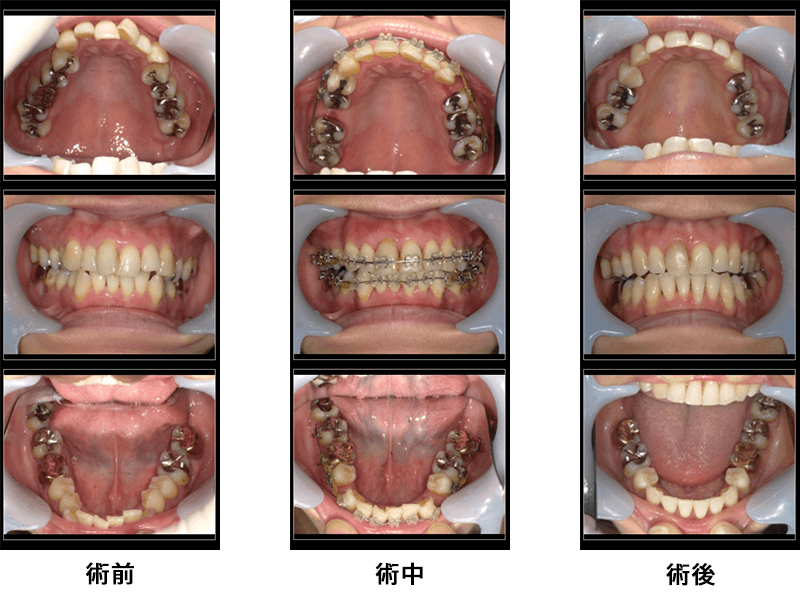

女性44歳

治療内容:ワイヤー全額矯正

金額:770,000円

来院理由:虫歯でしみるのと、歯並び相談

施術の副作用(リスク):

調整後は痛みを感じることがあります。ワイヤーが頬粘膜や口唇を傷つけることがあります。

咬みにくさを感じることがあります。歯が一時的に動揺することがあります。